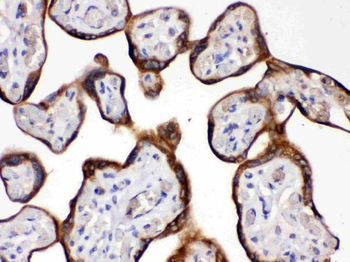

10 μg, 100 μg - Anti-CD44 Antibody [orb402179]

ELISA, FC, ICC, IF, IHC, IHC-Fr, WB

Human, Mouse, Rat

Rabbit

Polyclonal

Unconjugated

10 μg, 100 μg - Anti-PRDM1/Blimp1 Antibody [orb402200]